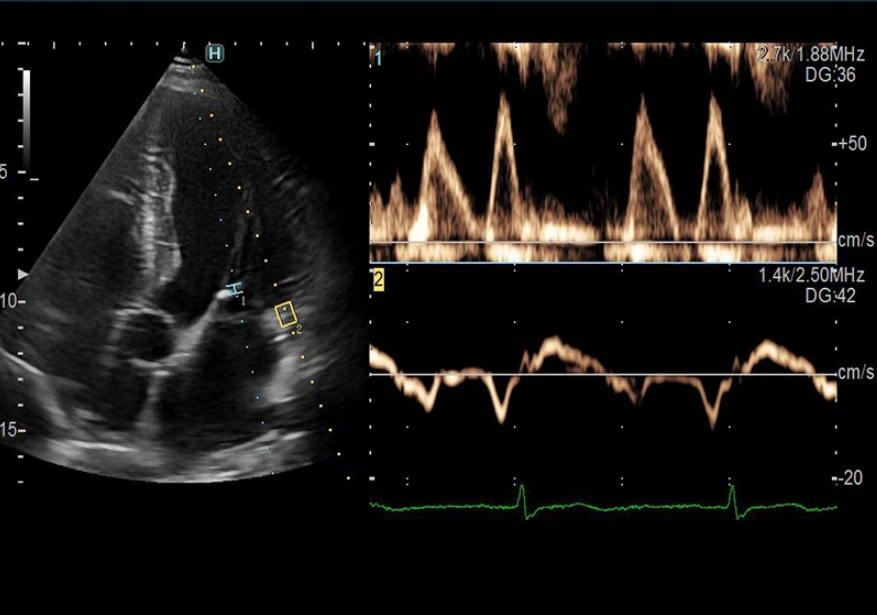

Khi có các biểu hiện nghi ngờ mắc bệnh tim các bác sĩ sẽ chỉ định siêu âm tim để xác định chẩn đoán bệnh

- Siêu âm tim - Doppler tim.